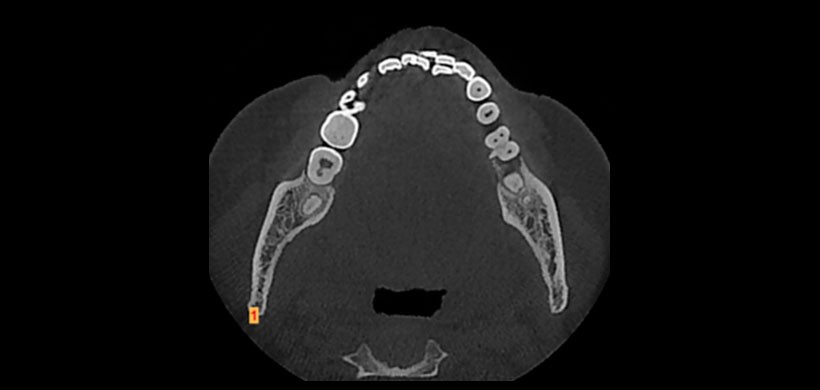

Al realizarse la tomografía computarizada de haz cónico detectó una una estructura de densidad dentaria en el área de furcación con una forma esferoide alargada de 1,8 mm de ancho y 8 mm de largo. (Figura 2)